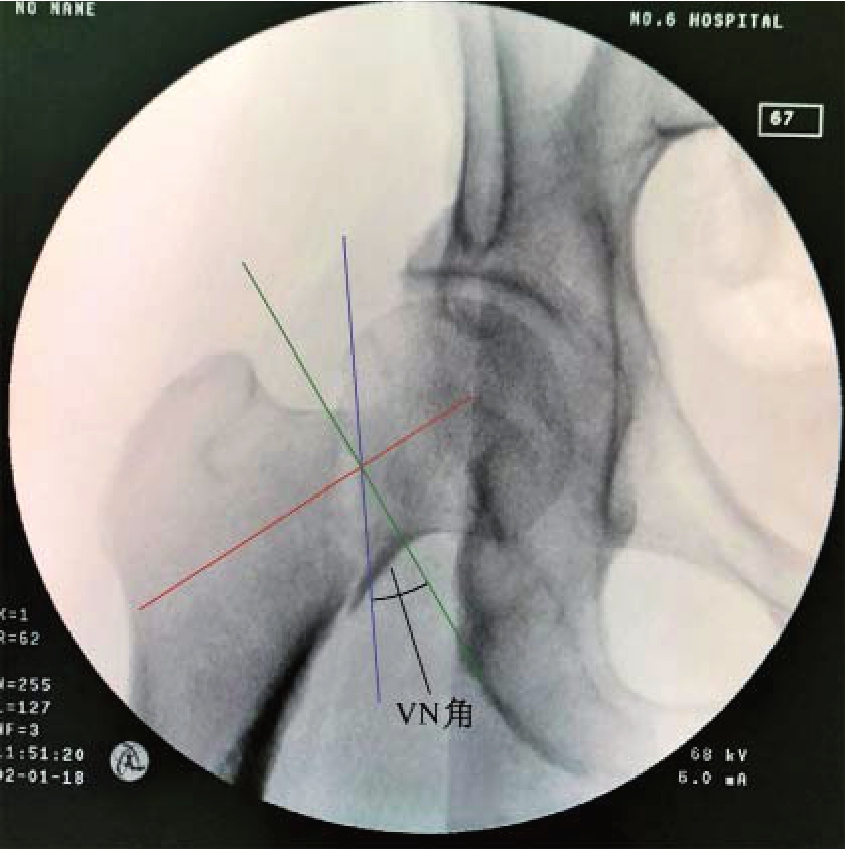

近期,上海交通大学附属第六人民医院骨科报道了一个新的角度,即骨折线与股骨颈轴线的垂线之间的夹角,称之为“颈垂角”(VN角)。VN角单纯用骨折线与股骨颈轴线的垂直角度来表示,更加简单直接地表达了单纯动力加压固定(平行于股骨颈轴线)与骨折线之间的关系(图9—2)。该观点认为,当骨折线与股骨颈轴线完全垂直时,VN角接近0°;当骨折线趋向垂直时,VN角的数值为正值;趋向水平时则为负值。基于骨折的VN角设计了一个新的分型系统,即将股骨颈骨折分为四型:Ⅰ型的VN角<0°;Ⅱ型 的VN角 为0°~10°;Ⅲ型 的VN角 为10°~15°;Ⅳ型 的VN角>15°。研究发现,当VN角>10°时,单纯空心钉内固定的失败率开始显著增高。当为Ⅳ型时,其内固定失败率达到了65.45%。这一研究结果以及分型系统为股骨颈骨折的内固定选择提供了很好的指导意义。

图9—2 VN角测量方法